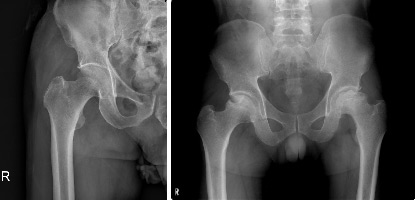

방사선학적 검사는 진단 확진에 도움이 됩니다. 엑스선 검사는 뼈와 같이 단단한 구조물을 보여주며, 대퇴 골두의 붕괴가 있는지 여부와 그 정도의 확인을 위해 촬영합니다.

(왼쪽) 건강한 고관절의 엑스선 영상. (오른쪽) 골괴사의 진행으로 대퇴골두의 붕괴가 진행된 엑스선 영상.